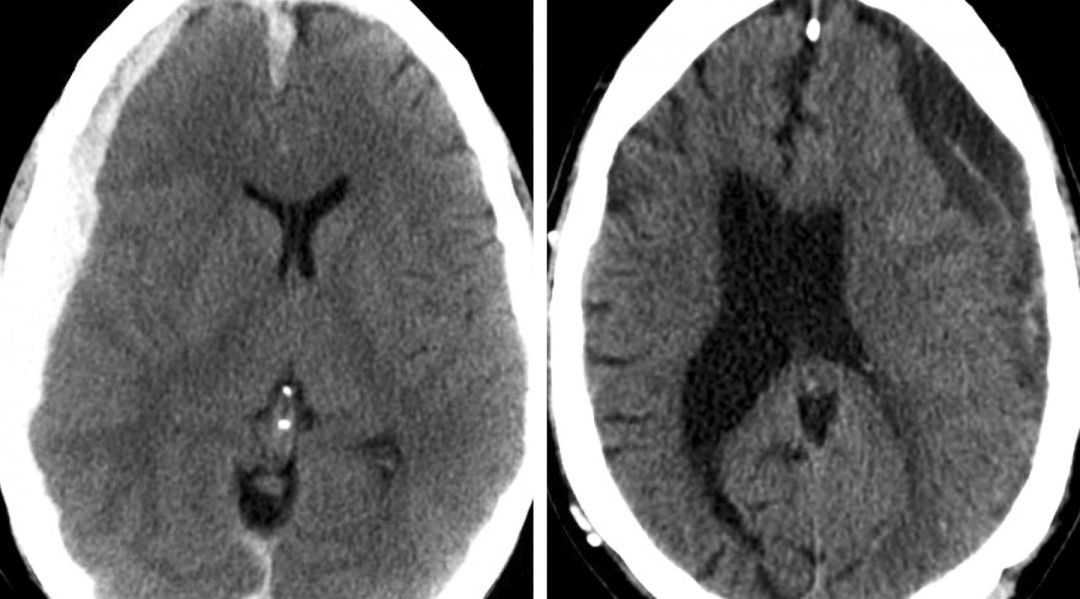

尽管患者入院就诊时可没有相对明显的神经功能障碍,但占位效应显著的巨大硬膜下血肿可导致突发的不可逆转的急性神经功能失代偿。在病情恶化时行急诊引流术可能无法改善患者术后的神经功能恢复情况。因此,对于无明显症状但占位效应显著的患者,应采取及时紧急的处理。

图7:这是一名不幸的年轻外院男性患者,仅表现为轻度的意识障碍(第一行图片,注意其右上角图像显示的早期脑疝征象)。考虑到患者平素规律服用阿司匹林,并有输注血小板的可能,手术被推迟至第二天进行。但该患者在第二天早晨病情突然恶化,遂于急诊行钻孔引流术。虽然血肿被充分清除,但由于患者术前突发脑疝可能导致了大脑弥漫性缺血(底行图片),患者最终死亡。